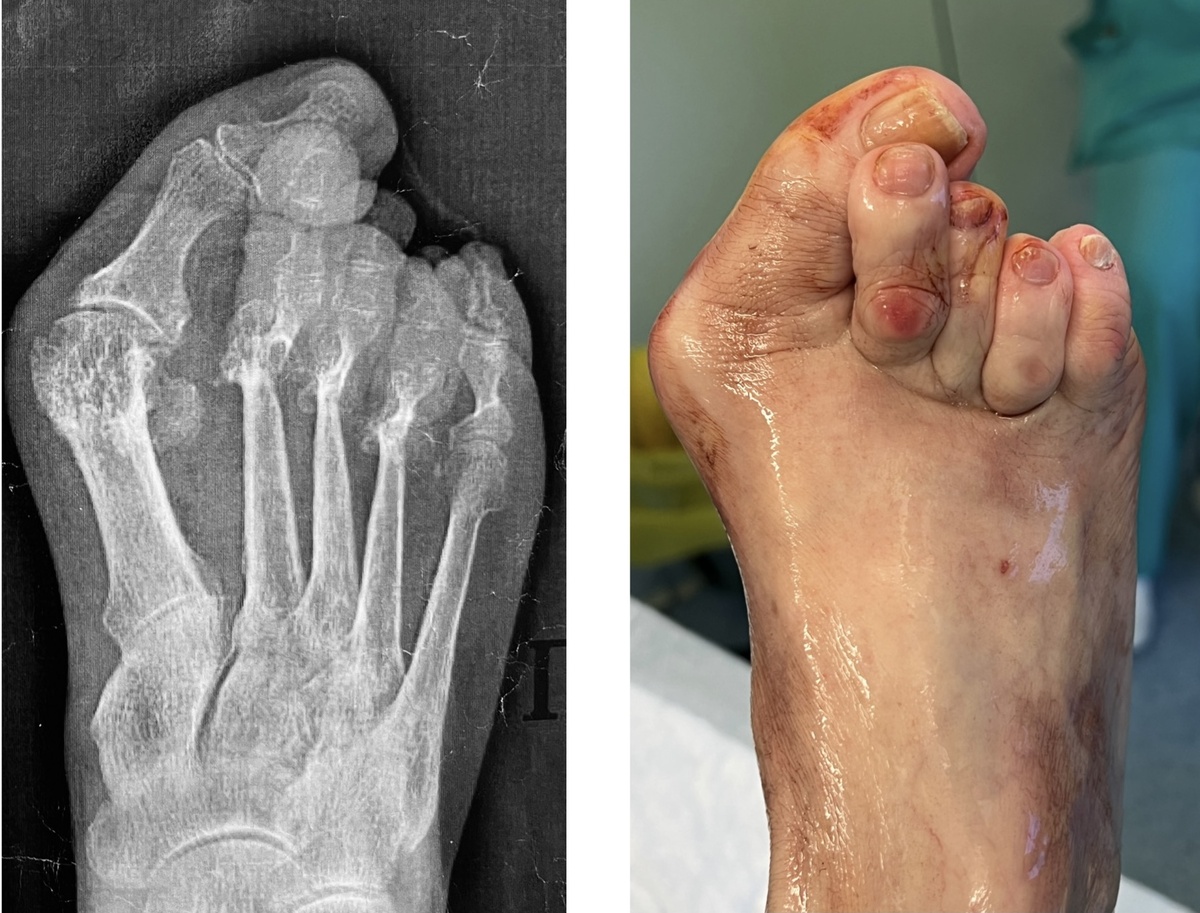

Начну издалека. Вчера показал фото стопы до и после операции. Сильно деформированная стопа. В части комментариев звучала следующая мысль: «бедная женщина, как же она ходила? она ведь мучилась от боли!!»

Выглядело это так:

Выглядит впечатляюще, НО: вторая стопа еще хуже, и ОБЕ стопы эту пациентку не беспокоили ВООБЩЕ. Только правая вот в этой части:

Именно этот натоптыш вызывал боль, и заставил обратиться ко мне. Хотите - верьте, хотите - нет, но это есть факт: если бы не боль в области натоптыша, женщина спокойно жила бы дальше со своими деформированными стопами.